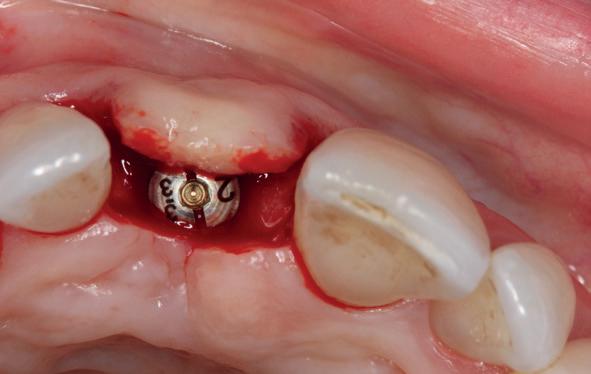

Implantologische behandelingen in het esthetische front vragen meer dan technische vaardigheid alleen. Ze vragen om overzicht, timing, vertrouwen en een team dat als vanzelf samenwerkt onder druk. Juist bij complexe casussen, waarin angst, infectie en hoge esthetische verwachtingen samenkomen, wordt zichtbaar hoe bepalend de rol van de tandartsassistent is.

Deze casus beschrijft een uitgebreide immediate implantaatbehandeling bij een patiënt die door meerdere collega’s werd geweigerd. Niet omdat de mogelijkheden ontbraken, maar omdat de complexiteit vroeg om een perfect afgestemde samenwerking. Het verhaal laat zien hoe de assistent in zo’n traject veel meer is dan een uitvoerende kracht of “mal”, maar een dynamische surgical guide die het proces mede stuurt, bewaakt en mogelijk maakt.De patiënt: wanneer alles samenkomt

Na het klinische onderzoek volgde het röntgenologisch traject. De CBCT liet precies zien wat we al vreesden: een front waarin het bot onregelmatig was, duidelijke radiolucenties rond de pijlers en een infectiegebied dat zich onder vrijwel de gehele brug had verspreid. Tegelijkertijd was er ook potentie. Net voldoende botstructuur om immediate implantaatplaatsing te overwegen, mits alles perfect gepland zou worden.